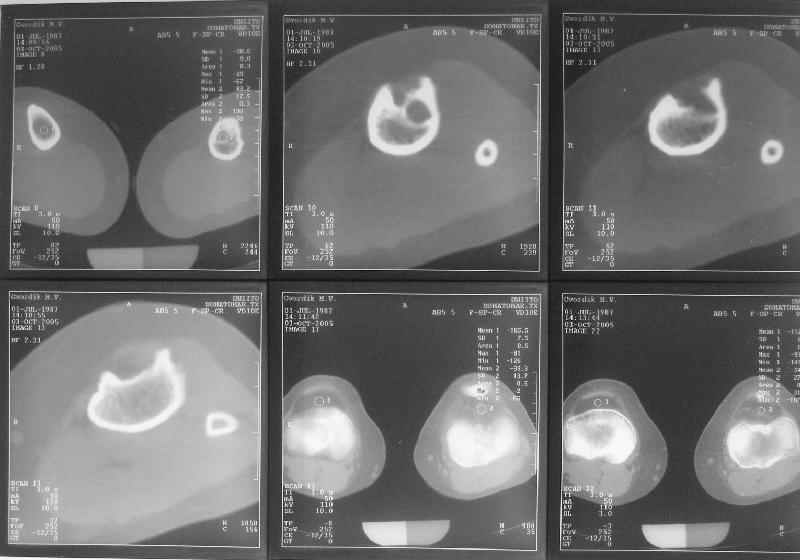

Продолжение обсуждения, начатого в октябре прошлого года (см. здесь) Наконец-то оперировали эту пациентку. Биопсию сделали - опухолевого ничего нет. Пока все участвовавшие в обследовании смежные специалисты и ортопеды сошлись, что это молокальная монооссальная фиброзная дисплазия. 20 марта наложили аппарат, сделали чрескожную остеотомию. К 3 апреля все докрутили. Сегодня заштифтовали. Начальные и итоговые снимки в приложении. Рекурвацию можно было еще немного больше устранить, и чуть кзади сместить диафиз. Но вроде и так ничего выглядит, по сравнению с тем, что было. Комментарии приветствуются.